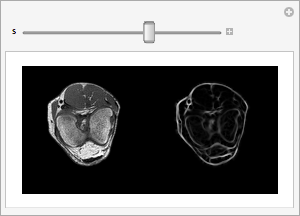

もとの膝の立体とフィルタ適用後の立体の各スライスを隣り合せに描画する.